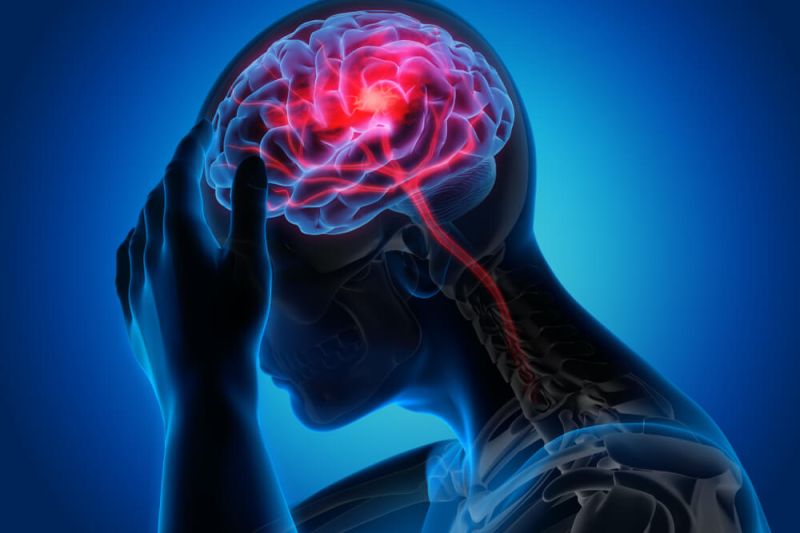

O carcinoma de mama (ou conhecido popularmente como câncer de mama) é o tipo mais incidente em mulheres em todo o mundo. Para 2022, são esperados que sejam diagnosticados 66.280 novos casos, segundo o INCA (Instituto Nacional de Câncer).

Ele também é a primeira causa de morte em mulheres no Brasil, apesar de sua ocorrência não ser restrita apenas a elas, podendo afetar também os homens.

Quando descoberto precocemente, ele pode ter mais de 90% de chances de cura. E, para isso, os tratamentos precisam ser direcionados para os tipos de carcinoma de mama. Neste artigo vamos trazer um guia completo com os tipos mais comuns e ajudar você a saber mais sobre o tema.

Importância do diagnóstico precoce do carcinoma

Como você viu ao longo deste artigo, o sucesso do tratamento do carcinoma depende diretamente de um diagnóstico precoce. Isso porque alguns tumores evoluem rapidamente e, assim, as chances de metástase são altas. Contudo, quando descobertos precocemente, podem ter chances de cura de mais de 90%.

Isso vale tanto para os mais tranquilos quanto para os que evoluem rapidamente. Além disso, os tratamentos tendem a ser menos agressivos de acordo com o estágio do tumor. Por exemplo, quando o tumor está nos estágios iniciais, o paciente pode não precisar realizar a quimioterapia antes do procedimento cirúrgico.

Além disso, mesmo nos quadros mais avançados, quanto antes ele for descoberto, menos prejuízos há para a saúde e qualidade de vida do paciente.